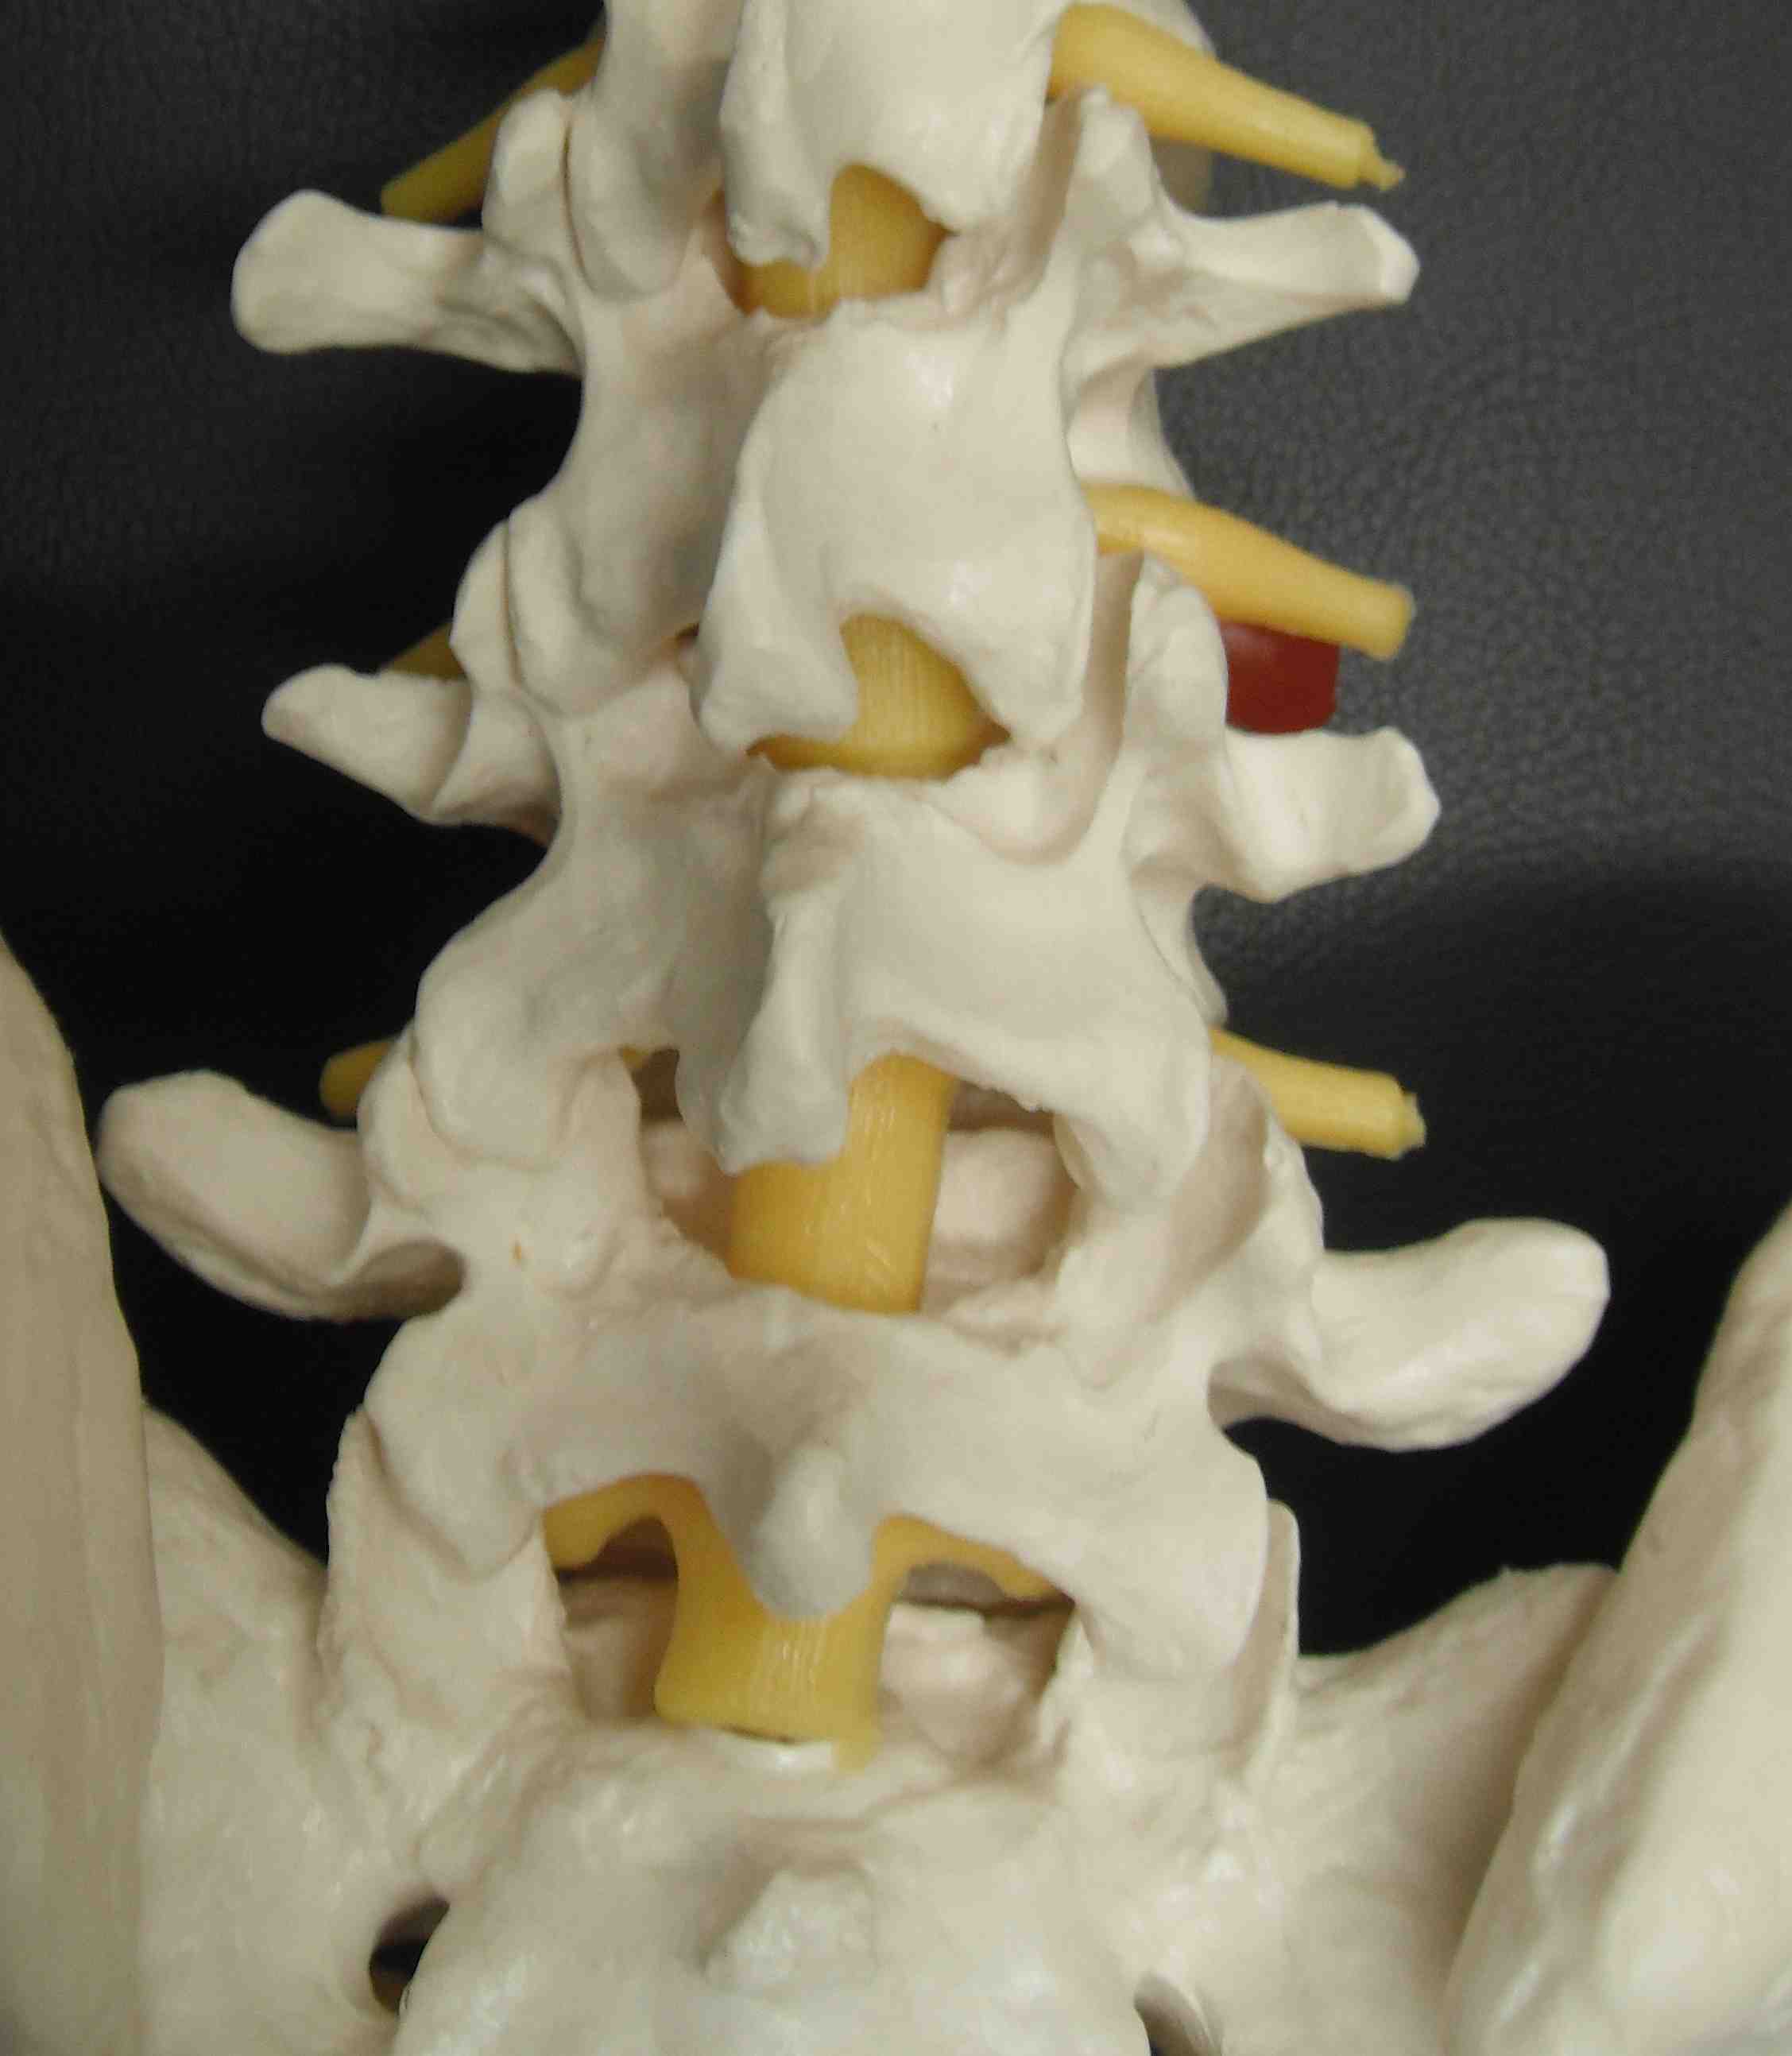

Anatomy

L4/5 disc at level of facet joints

Interlaminar space is below disc

- have to take inferior aspect of superior lamina

Pedicle and transverse process at same level

Disc usually on one side